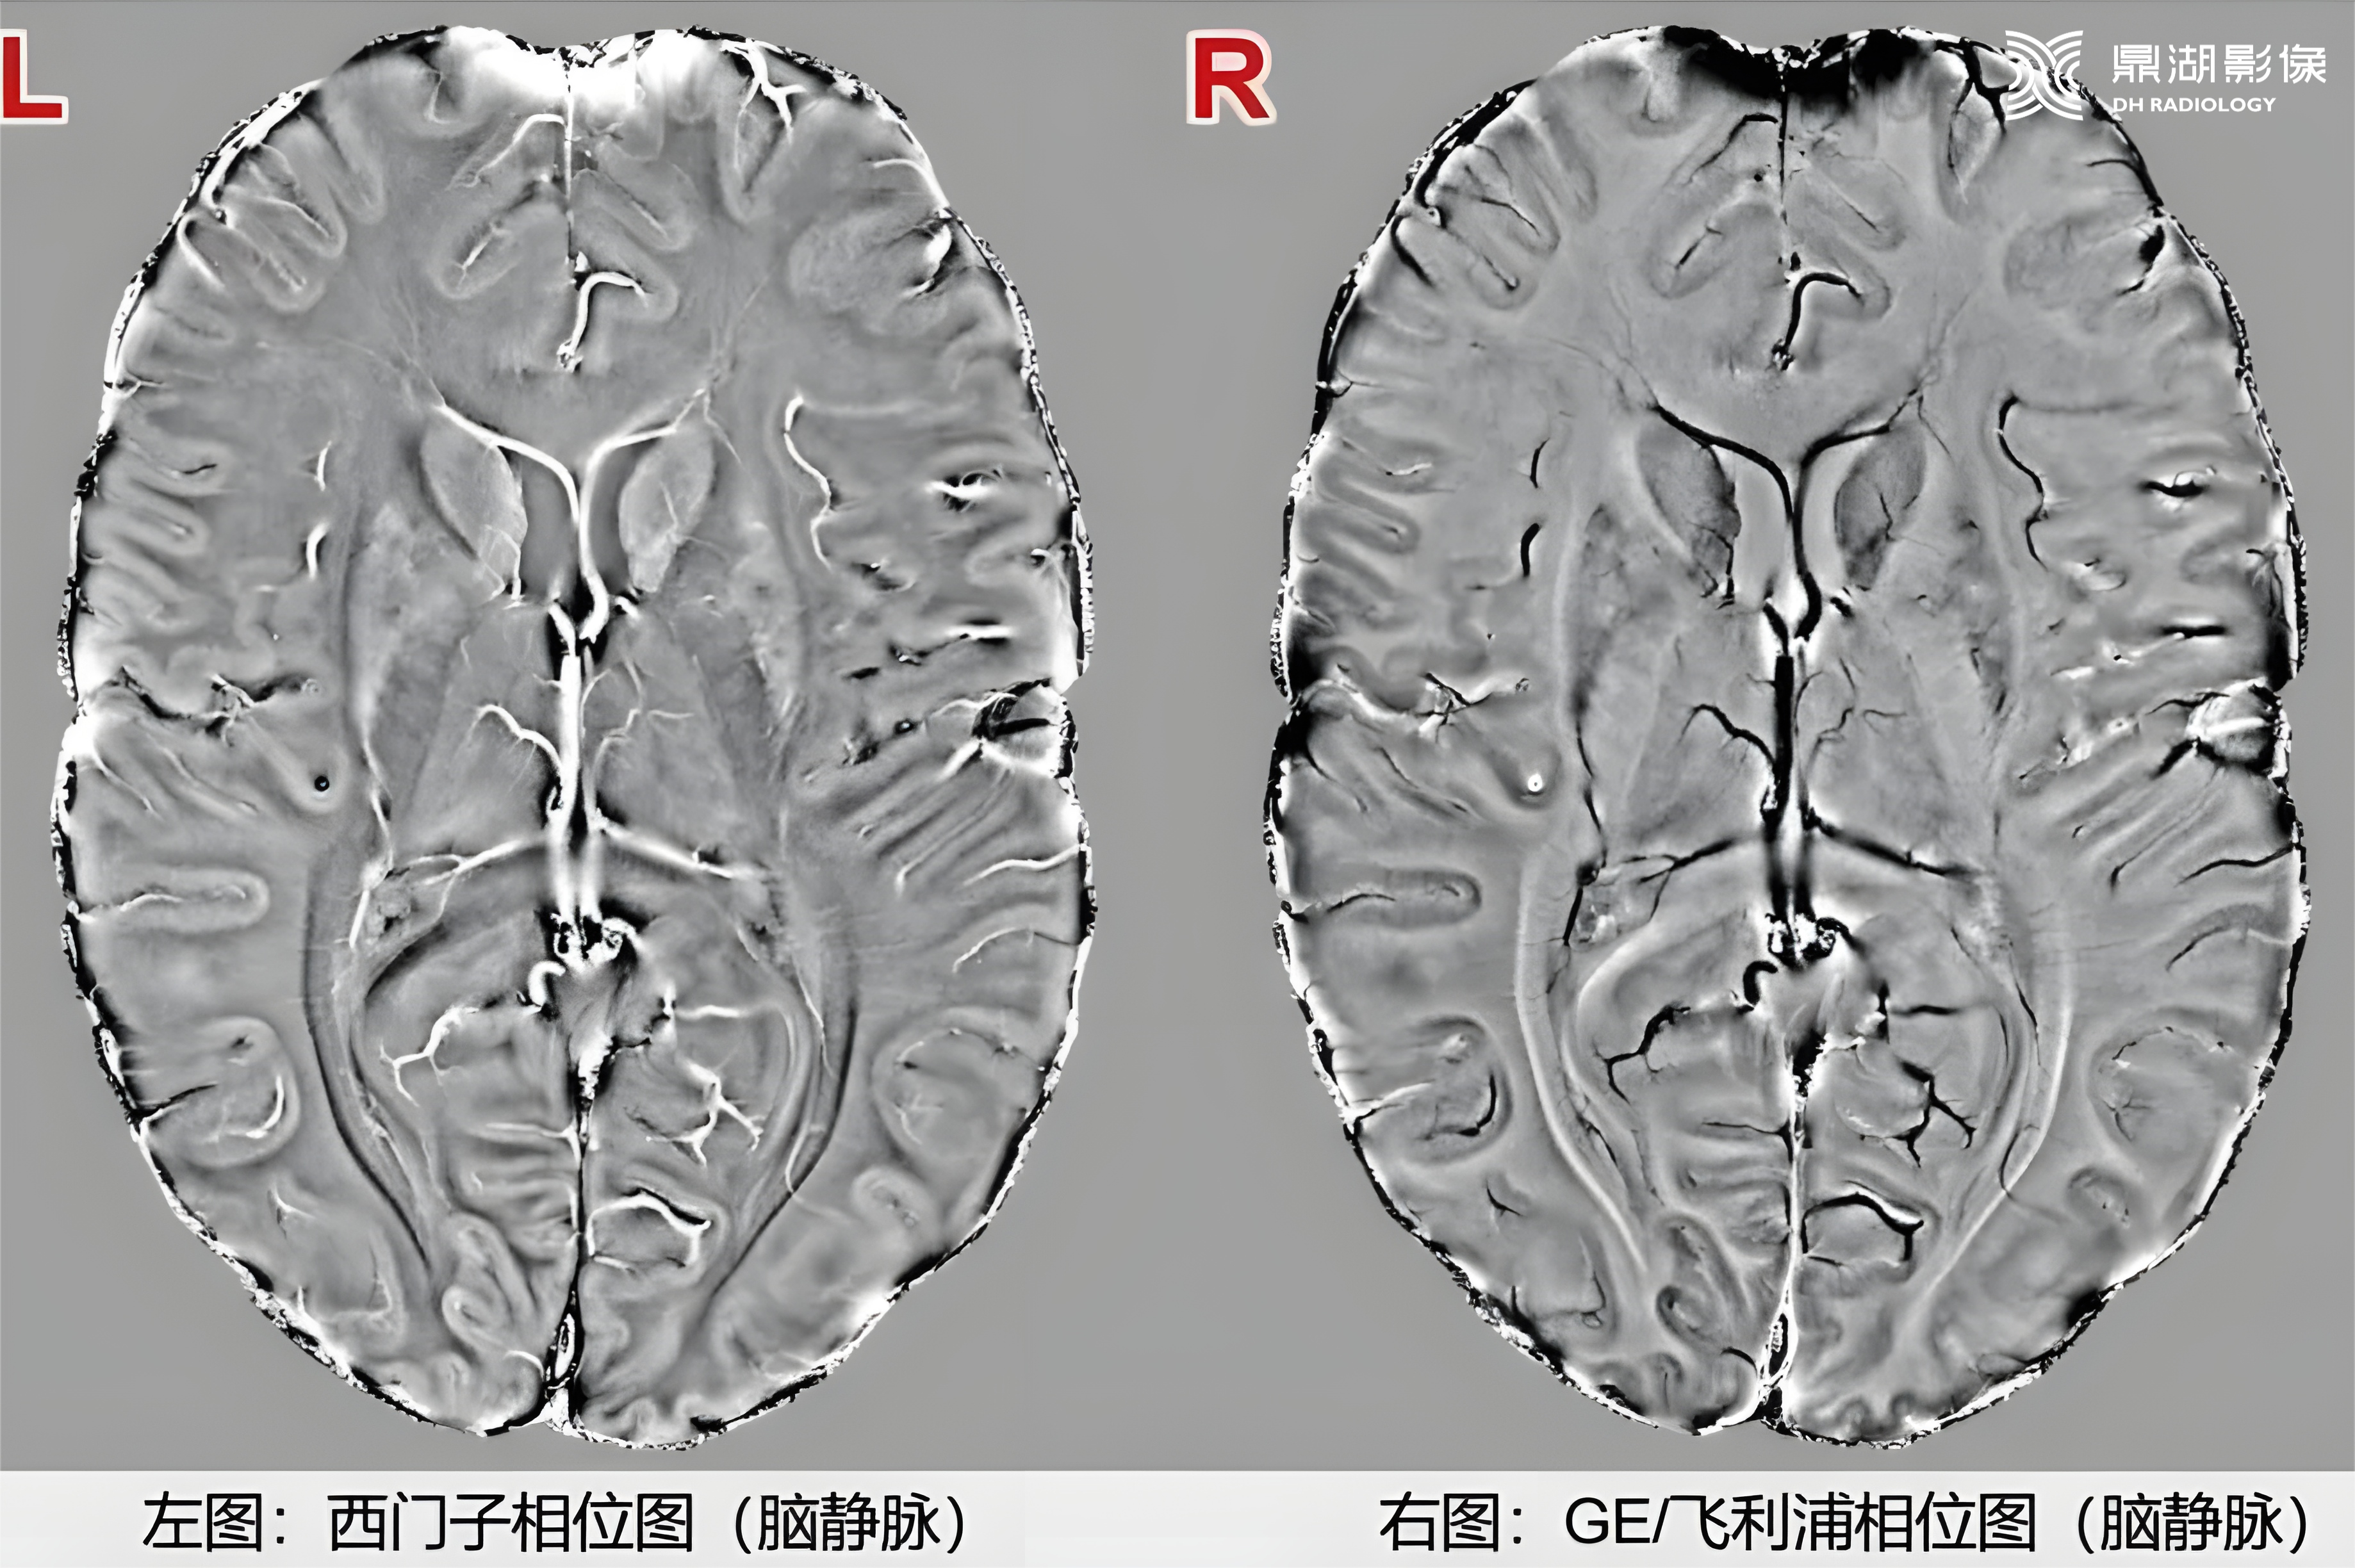

在SWI图像判断时,西门子设备上钙化在相位图呈低信号,而GE、飞利浦上呈高信号,这是因为不同厂商采用的相位坐标系统不同

不同厂商磁共振设备的SWI相位图信号差异,源于相位坐标系的左右手系统区别:

右手坐标系(飞利浦、GE)

坐标特性:顺磁性物质产生负相移,相移越大相位图越亮(灰度越高)。

信号表现:

出血(顺磁性):相位图呈低信号,幅度图及 MIP 图呈低信号。

钙化(抗磁性):相位图呈高信号,幅度图及 MIP 图呈低信号。

02

左手坐标系(西门子、佳能)

坐标特性:顺磁性物质产生正相移,相移越大相位图越亮(灰度越高)。

出血(顺磁性):相位图呈高信号,幅度图及 MIP 图呈低信号。

钙化(抗磁性):相位图呈低信号,幅度图及 MIP 图呈低信号。

西门子与GE机器—出血图像对比